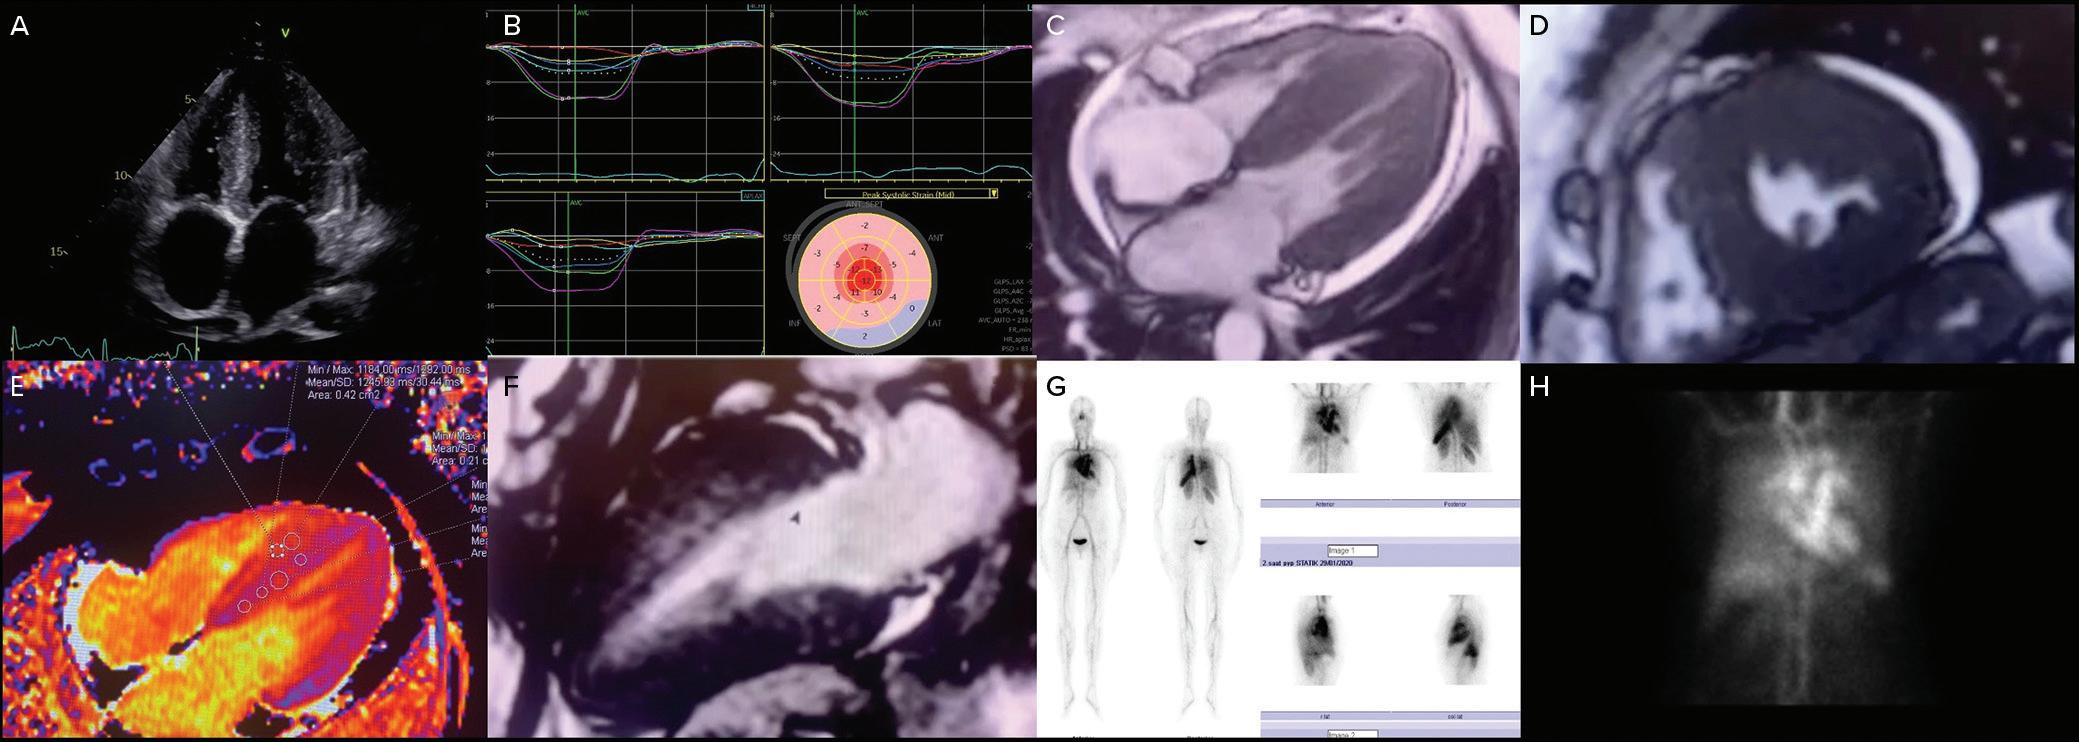

Imaging in Heart Failure with Preserved Ejection Fraction: A Multimodality Imaging Point of View

Serkan Ünlü, Özge Özden and Ahmet Çelik

Role of Imaging in Cardiomyopathies

Vincenzo Castiglione, Alberto Aimo, Giancarlo Todiere, Andrea Barison, Iacopo Fabiani, Giorgia Panichella, Dario Genovesi, Lucrezia Bonino Alberto Clemente, Filippo Cademartiri, Alberto Giannoni, Claudio Passino, Michele Emdin and Giuseppe Vergaro

DOI: https://doi.org/10.15420/cfr.2022.26